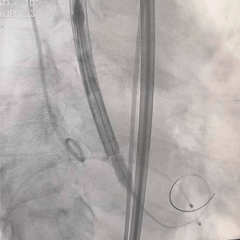

术中影像

8mm外周球囊扩张髂动脉狭窄处

根部造影可见大量反流

TF29瓣膜,0位初始定位